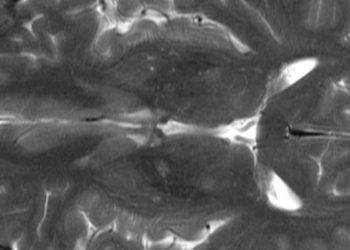

The idea behind the keto diet is that it alters the way that our body uses energy. This results in the production of ketones, instead of carbohydrates, which can be used by the rest of the body for energy. These ketones can enter the brain, and potentially improve the transmission of messages between brain cells, thereby helping in epilepsy and mental health conditions. The new study showed significant improvements in participants’ overall metabolic health, as well as huge improvements in the severity of their mental illnesses. Participants also experienced greater life satisfaction and improved functioning, showing that the effect of the keto diet, and potentially other lifestyle measures, may be substantial for mental health.